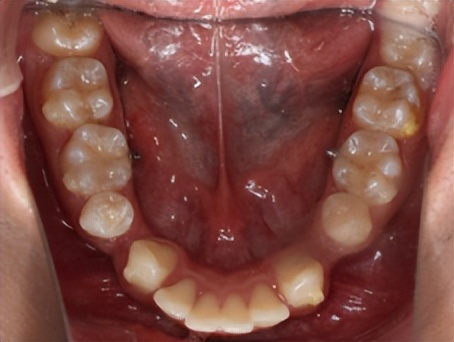

一般来说,正畸拔牙以后的间隙可以被两个方面的牙齿移动所关闭,一方面前牙向后移动,另一方面是后牙向前移动。

根据模型测量和X线影像分析结果,如果牙列拥挤严重或前突,则需要拔牙间隙更多的用于前牙往后移动;如果后牙咬合关系不佳,则通过后牙更多地向前移动来调整。

正畸医生通过矫治器的作用有效控制牙齿移动,最终将拔牙间隙完全关闭,因此是不需要镶牙的。